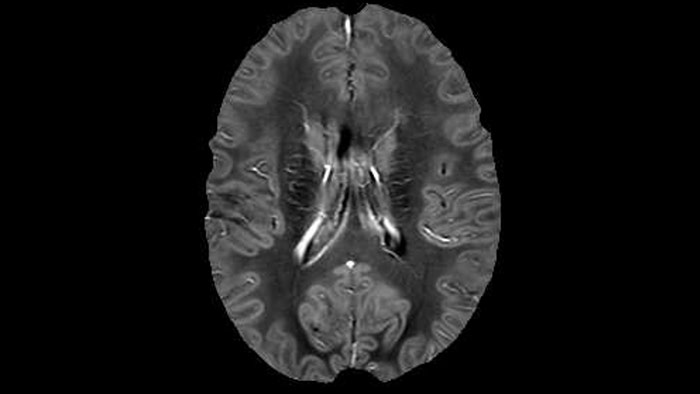

He says the accelerated scanning is achieved via the use of Compressed SENSE and MultiBand SENSE. “We can use Compressed SENSE acceleration factors of about 10 on a 3D FLAIR for instance, which is quite remarkable compared with what we saw with the Achieva. With 3D FLAIR, we can push the spatial resolution to 0.3 cubic mm and it works. Previously, our 3D FLAIR scans lasted about 8 minutes, but now with Elition they are five minutes. The SNR is also visibly better. Our SWI and QSM scans look fantastic. Also, since a lot of neuroimaging is EPI based, using the MultiBand SENSE technique can increase temporal resolution and make it possible to run complicated DTI scans relatively quickly.”

Sagittal 3D FLAIR with 0.3 mm3 voxel volume acquired in 5:12 min. using Compressed SENSE showing a (juxta)cortical MS lesion.

QSM based on a Compressed SENSE multi-echo SWI.